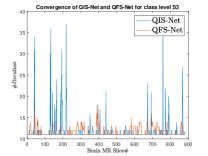

where, represents the true interconnection weight terms of the inter-connection weights as expressed using the Hadamard gate () at an instance (). is a coherent error function of and . Convergence analysis of the proposed qutrit-inspired QFS-Net is provided in Appendix Section -A and demonstrated experimentally with qubit embedded QIS-Net [39] as shown in Figure 3. It can be summarized that the convergence of the QFS-Net is faster than that of the QIS-Net and also follows super-linearity. This claim is also substantiated by the number of iterations required to converge for each image slice in QFS-Net and QIS-Net as illustrated in Figure 4.